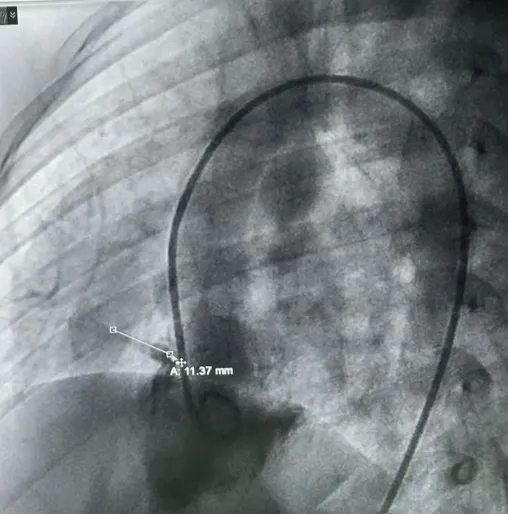

术中造影

术中造影复测缺损左室面破口3.9mm,隧道长11.37mm,判定为长隧道型室间隔缺损。